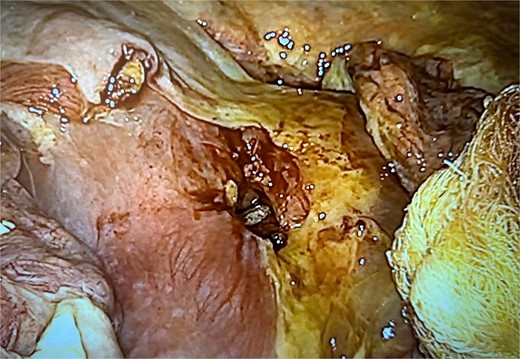

Exploratory laparoscopy revealed approximately 2000 mL of purulent fluid and an MU perforation (Fig. 5). The defect was repaired as described above, followed by abdominal cavity aspiration and irrigation (Figs 6 and 7). He remained in the intensive care unit for 48 h with symptomatic improvement and was discharged 6 d postoperatively.